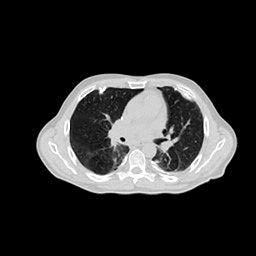

In this section, the reconstruction performance of our proposed framework under few-view conditions will be tested. For the parallel and fan beam geometry, the number of views increases from to , uniformly distributing from to and to respectively. Such settings provide a complete benchmark of reconstruction performance, ranging from extremely sparse to relatively complete, full-view CT reconstruction. The experiment results are shown in Fig.5. Additionally, the ground truth, few-view ( views), and full-view ( views) CT reconstruction results of different methods are shown in the first and third rows of Fig.7 (parallel-beam, LIDC-IDRI dataset), and Fig.8 (fan-beam, LIDC-IDRI dataset).

To test the proposed framework’s performance on limited-angle reconstruction, we redo the experiment in the above section with the angular range changing from to for parallel-beam geometry and to for fan-beam geometry, one projection per degree. The experiment results are shown in Fig.6. Also, the ground truth and the limited-angle CT reconstruction results of different methods are shown in the row of Fig.7 (parallel-beam, LIDC-IDRI dataset), and Fig.8 (fan-beam, LIDC-IDRI dataset).

Conventional IR methods, even those with the help of regularizations such as total variation, are prone to artifacts when constrained by few-view and limited-angle conditions. However, as illustrated in the first and second rows of Fig.7b, and Fig.8b, these images still contain meaningful information which can be used to guide DIP related reconstruction methods, despite the presence of artifacts.

DIP related methods, which leverage the hierarchical structure of neural networks as a powerful prior, can better handle the aforementioned challenge. However, the original DIP method has its own limitations. It cannot generate detailed images or effectively enhance its accuracy as the number of measurements increases. For instance, in Fig.5a, the ASD-POCS algorithm achieves an approximate SNR gain of dB when the number of views increases from to , while the DIP method only attains an approximate dB gain. This problem is also shown in the last row of Fig.7, and Fig.8. Moreover, the DIP method may produce neural network specific artifacts, as shown in Fig.7d, Fig.8d, and Fig.12c. These artifacts are particularly problematic as they are often considered more undesirable than streak artifacts. Radiologists, with their professional experience, can interpret and account for streak artifacts, whereas network specific artifacts may prove more challenging to identify and address.

The proposed RBP-DIP framework combines the two approaches utilizing the newly devised RBP connection so that inherits the benefits of both methods. In Fig.4, the RBP-DIP method’s attainment of a 5dB SNR enhancement over the ASD-POCS method, despite exhibiting a larger loss. This implies that the improvement is not caused by the further minimization of the loss function but by the ability to choose a more reasonable reconstruction result from all candidates with similar losses. This is precisely the direct evidence of the successful combination of conventional IR and deep image prior in the proposed RBP-DIP framework. Subsequently, the improvement surpassing the original DIP method indicates the efficacy of the RBP connection. Moreover, by employing the RBP connection, neural network specific artifacts can be rectified effectively. As a result, substantial advancements can be shown in Fig.5, Fig.6, Fig.7, and Fig.8.